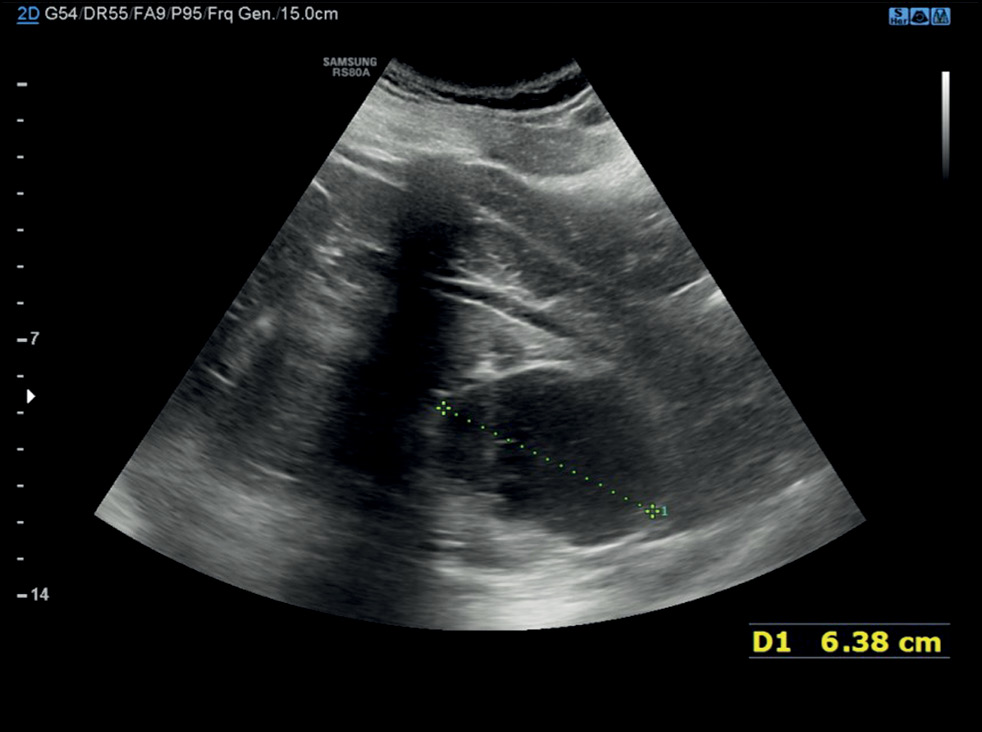

A case of spontaneous liver rupture and the role of imaging: from computed tomography to interventional treatment

Abstract

Hepatic parenchymal rupture is a rare but potentially fatal condition that can be caused by trauma, iatrogenic factors, spontaneous causes, etc. This case report describes the diagnostic and therapeutic steps employed in a patient with spontaneous hepatic parenchymal rupture. An older woman came to the emergency department with diffuse stomach pain. After clinical evaluation, she underwent computed tomography. The first computed tomography did not reveal a full-blown parenchymal rupture. Owing to data ambiguity, indicating that the abdominal discomfort could be caused by renal or biliary colic, obtaining an early diagnosis was very difficult. In truth, only few hypodense oval shapes with characteristic suprafluid densitometry were found in the liver parenchyma. However, after a few days, the discomfort persisted, and as the condition worsened, the patient underwent additional radiological examinations, which revealed the rupture of the liver parenchyma that required arteriography, and a long hospital stay until clinical resolution.